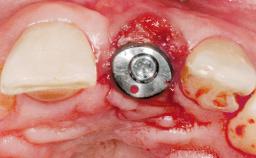

Immediate Placement of an Implant in a Maxillary Left Central Incisor Site

| # of Implants | 1 |

| Type of Implants | One-Piece |

| Attachment | One-Piece |

| Placement Protocol | Immediate implant placement |

| Tooth Site | Maxillary incisor or canine |